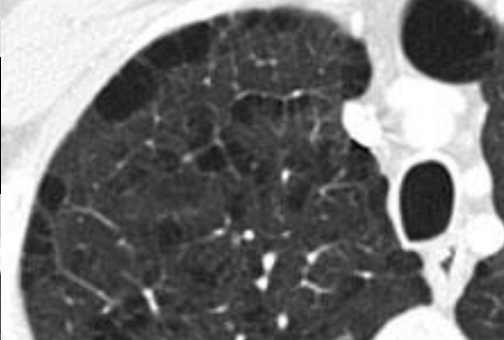

Centrolobulillar